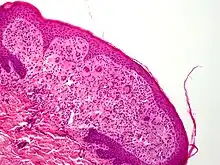

- Aspect externe : ces tumeurs se présentent comme des papules (rondes à ovales) nettement délimitées, lisses

Elles sont fermes (consistance de caoutchouc)[10].

Leur couleur, rose à rouge, est nuancée de jaune et tend à virer au jaune-brun avec le temps[10] ; - Localisation : Les papules apparaissent plus souvent sur la tête et le cou, et moins souvent sur le haut du tronc et les membres[13] et très exceptionnellement sur les muqueuses buccales (souvent après l'âge de 3 ans sur les côtés de la langue ou milieu du palais, pouvant s'ulcérer et saigner)[10], parfois hyperkératosiques ou prenant des formes géantes, ou pédiculées ou même (exceptionnellement) lichénoïdes généralisées[10].

- Aspect histologique : La nature de l'infiltrat diffère selon l'âge de la lésion. L'aspect inflammatoire est moins visible (avec cytoplasme homogène et éosinophilique ou amphophilique) dans les lésions récentes. Ensuite, la part de l’infiltrat inflammatoire augmente et le cytoplasme des histiocytes est vacuolé et xanthomateux. Quand la lésion guérit elle est caractérisée par des fibroblastes et une fibrose. Les cellules géantes sont plus rares dans les lésions précoces et vieilles[14]. Des noyaux atypiques et des figures mitotiques sont parfois visibles [15]. L’activité mitotique est plus visible dans les lésions jeunes précoces[14].

- Taille : variable ; de 5 millimètres de diamètre et de quelques mm d'épaisseur à une tumeur bien visible de plusieurs centimètres de large (jusqu'à 2,5 cm[2] , avec quelques rares cas de forme géante (macronodulaires, jusqu'à 10 cm pouvant être confondues avec un hémangiome type « Cyrano » [16]) ; des cas atypiques existent, avec « éruptions lichénoïdes, réticulées, maculopapuleuses, en plaque, linéaires »[2].

- le xanthogranulome est plus souvent seul (60 % à 82 % des cas[10]), et présent sur la tête (sur le cuir chevelu éventuellement), le cou, tronc et membres.

Si la XGJ touche aussi le tissu sous-cutané (tissu mou profond dans 5 % des cas[10], plus souvent sur tête et au cou[17]), on sent à la palpation une masse nettement limitée, qui peut gêner le patient, la peau en regard pouvant ne pas être modifiée ou devenir jaunâtre[18]. - Des télangiectasies sont parfois (rarement) observées en périphérie ou sur la tumeur [10]. ;